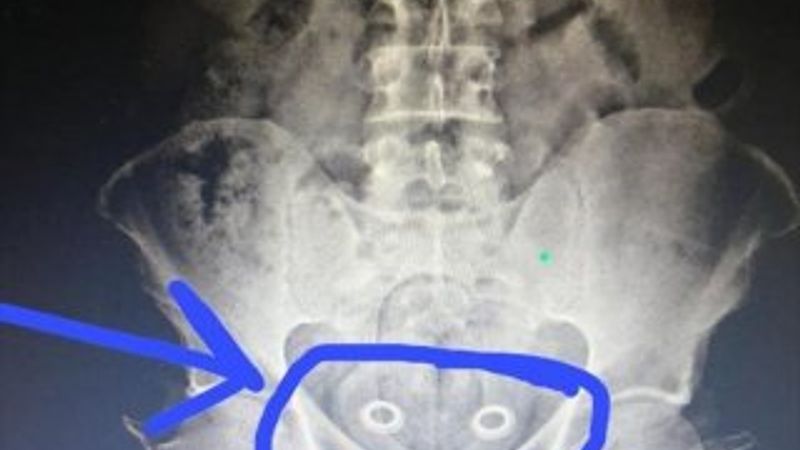

MİDE VE BAĞIRSAKLARINDAN ÇIKTI

Burada çekilen röntgen sonucu İran uyruklu A.P.'nin mide ve bağırsaklarında kapsüller içerisinde 107.92 gram metafetemin, folyoya sarılı 3 gram metamfetamin, 64 gram esrar tespit edildi. Gözaltına alınan İran uyruklu A.P. ile beraberindeki N.Ş., Ö.A., M.Y., Ş.K.'nin emniyetteki işlemleri sürüyor.